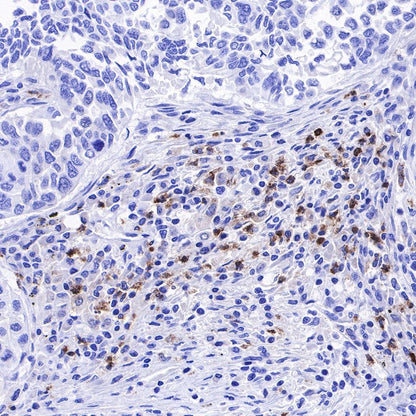

IHC shows positive staining in paraffin-embedded human colon cancer. Anti-Lysozyme antibody was used at 1/100 dilution, followed by a HRP Polymer for Mouse & Rabbit IgG (ready to use). Counterstained with hematoxylin. Heat mediated antigen retrieval with Tris/EDTA buffer pH9.0 was performed before commencing with IHC staining protocol.